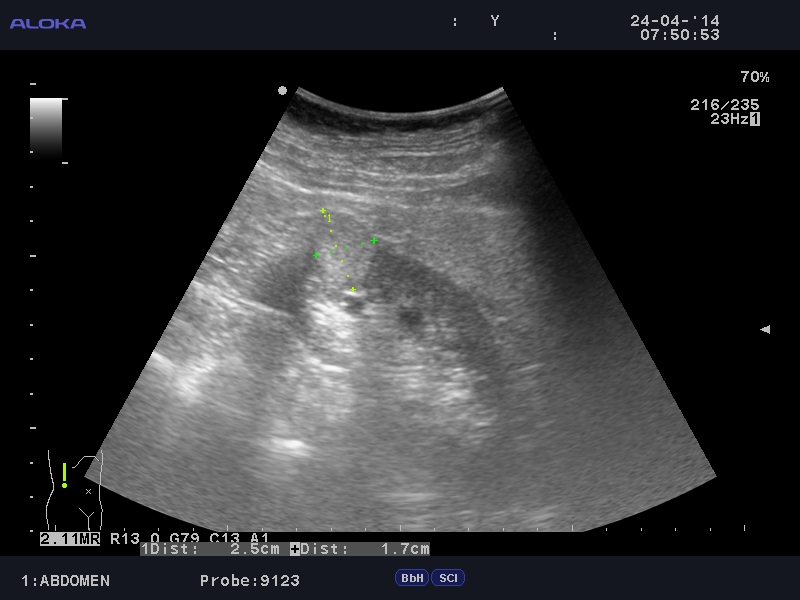

Онкоцитома почки - УЗИ

Женщина 76 лет. Жалоб не предъявляет.

Renal oncocytoma